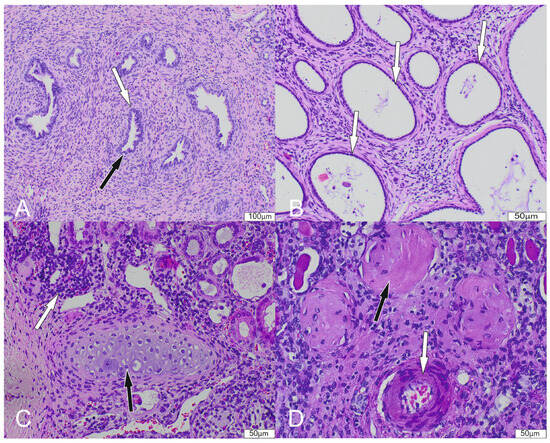

3.3. Histopathology